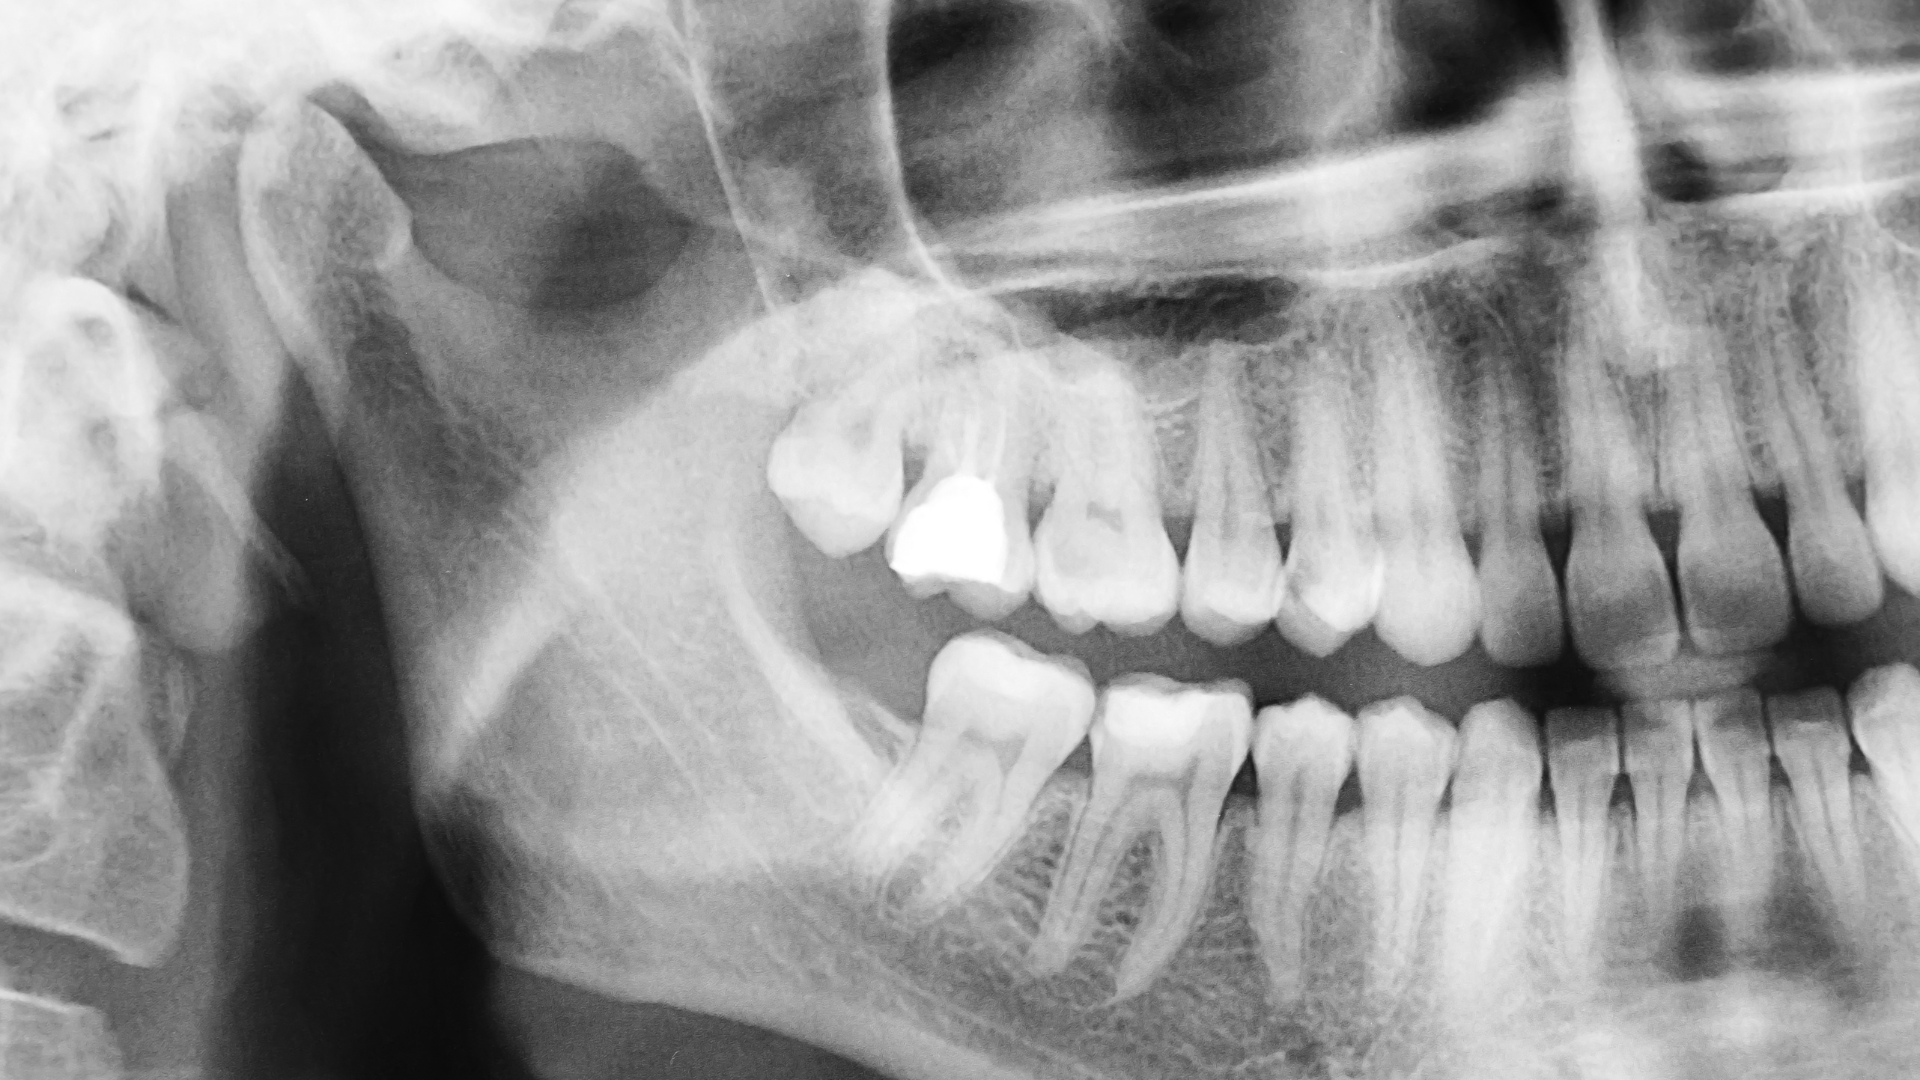

矯正治療では、歯や骨の状態を確認するためにレントゲン撮影が必要になることがあります。

妊娠中でも、防護エプロンを使用することで撮影自体は可能とされていますが、

時期や必要性を慎重に判断することが大切です。

また、この時期はレントゲン撮影や薬の使用についても配慮が必要になります。